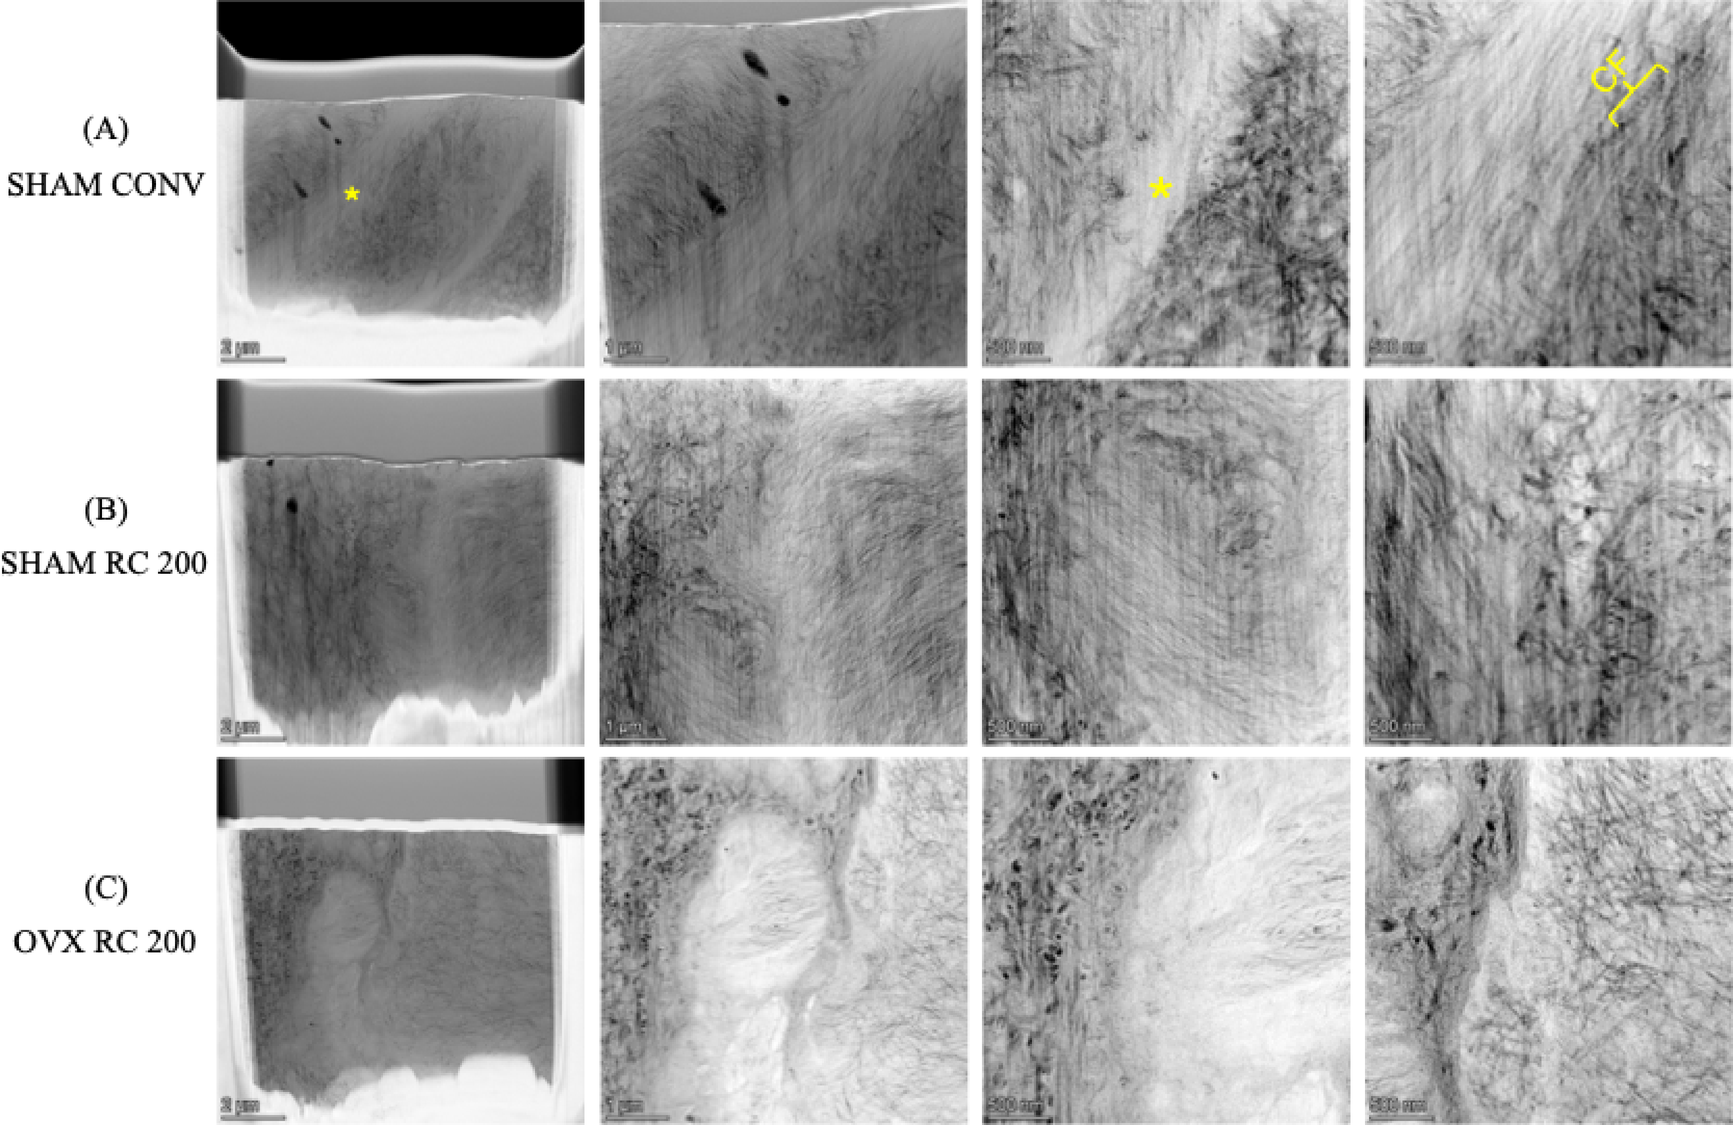

Fig. 10

HAADF-STEM images of the interface between new woven bone and pre-existing old bone for SHAM CONV, SHAM RC 200, and OVX RC 200. From left to right: Low magnification to higher magnification. Note that the new bone is located on the left side while the old bone is located at the right side of the images. Note the cement-line-like interface marked by an asterisk. CF = Collagen fibril.